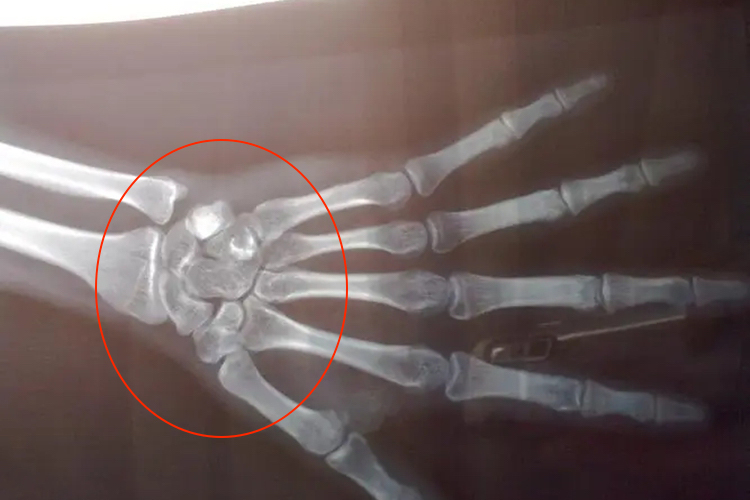

骨骼闭合后,通常情况下身高不会再明显增长。人的身高增长主要依赖于长骨两端的骨骺软骨细胞不断分裂增殖,使骨骼不断延长。当骨骺与骨干完全融合,骨骺线闭合,意味着骨骼的纵向生长潜力基本消失。

- 骨骼闭合是一个生理过程,受多种因素影响,包括遗传、营养、激素水平和生活环境等。一旦骨骼闭合,意味着身体已经完成了自然生长的阶段。